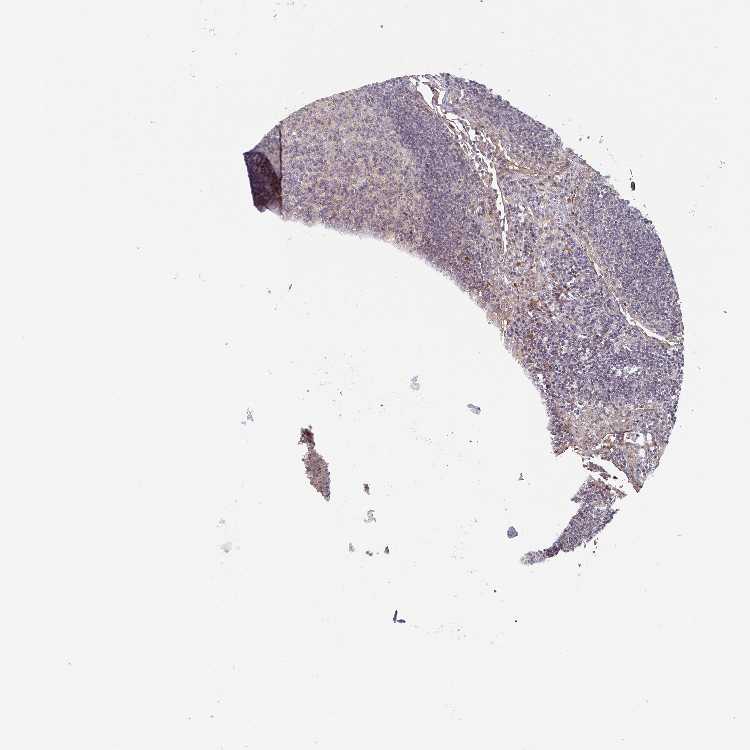

LYMPH NODE - Antibody stainingi

Antibody staining in the annotated cell types in the current human tissue is reported as not detected, low, medium, or high, based on conventional immunohistochemistry profiling in selected tissues. This score is based on the combination of the staining intensity and fraction of stained cells.

Each image is clickable and will lead to virtual microscopy that enables deeper exploration of all samples and also displays staining intensity scores, fraction scores and subcellular localization as well as patient and tissue information for each sample.

Antibody HPA042378

Germinal center cells Not detected

Non-germinal center cells Not detected